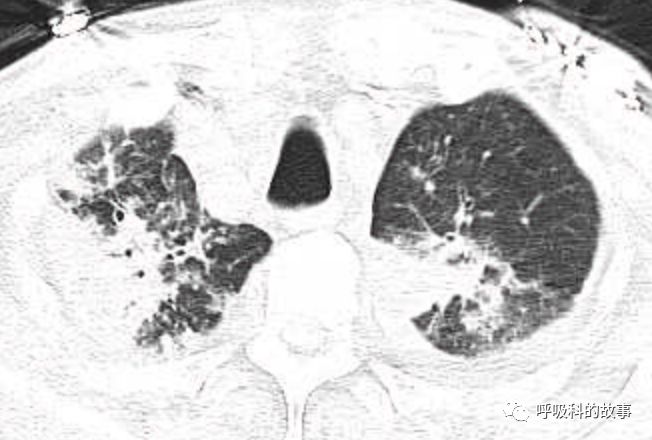

肺部CT如下:

以上的CT给我第一眼的感觉是肺炎,再结合患者有发热和血炎症指标明显增高,肺炎的诊断应该没有问题,但是胸水又是漏出液,结合脑钠肽增高和患者有胸闷气急的症状,心功能不全的诊断也能成立。在某些层面,肺部实变影以内中带为主,还要考虑肺水肿的诊断。入院后给予患者美罗培南抗感染、托拉塞米利尿治疗,以及化痰、雾化处理,患者体温在入院后三天就正常了,入院第五天复查NT-proBNP3390pg/ml;血常规示白细胞 13.5*10^9/L,中性粒细胞81.8%,淋巴细胞13.2%,超敏C-反应蛋白 25mg/L;电解质示钠 160mmol/L,氯 111mmol/L 。虽然炎症指标和心功能指标均有好转,但患者却仍旧精神差,每次查房时仍然表现嗜睡状,家属也反映患者不论白天还是夜晚多数时间不是太清醒。那么问题出在哪里呢?